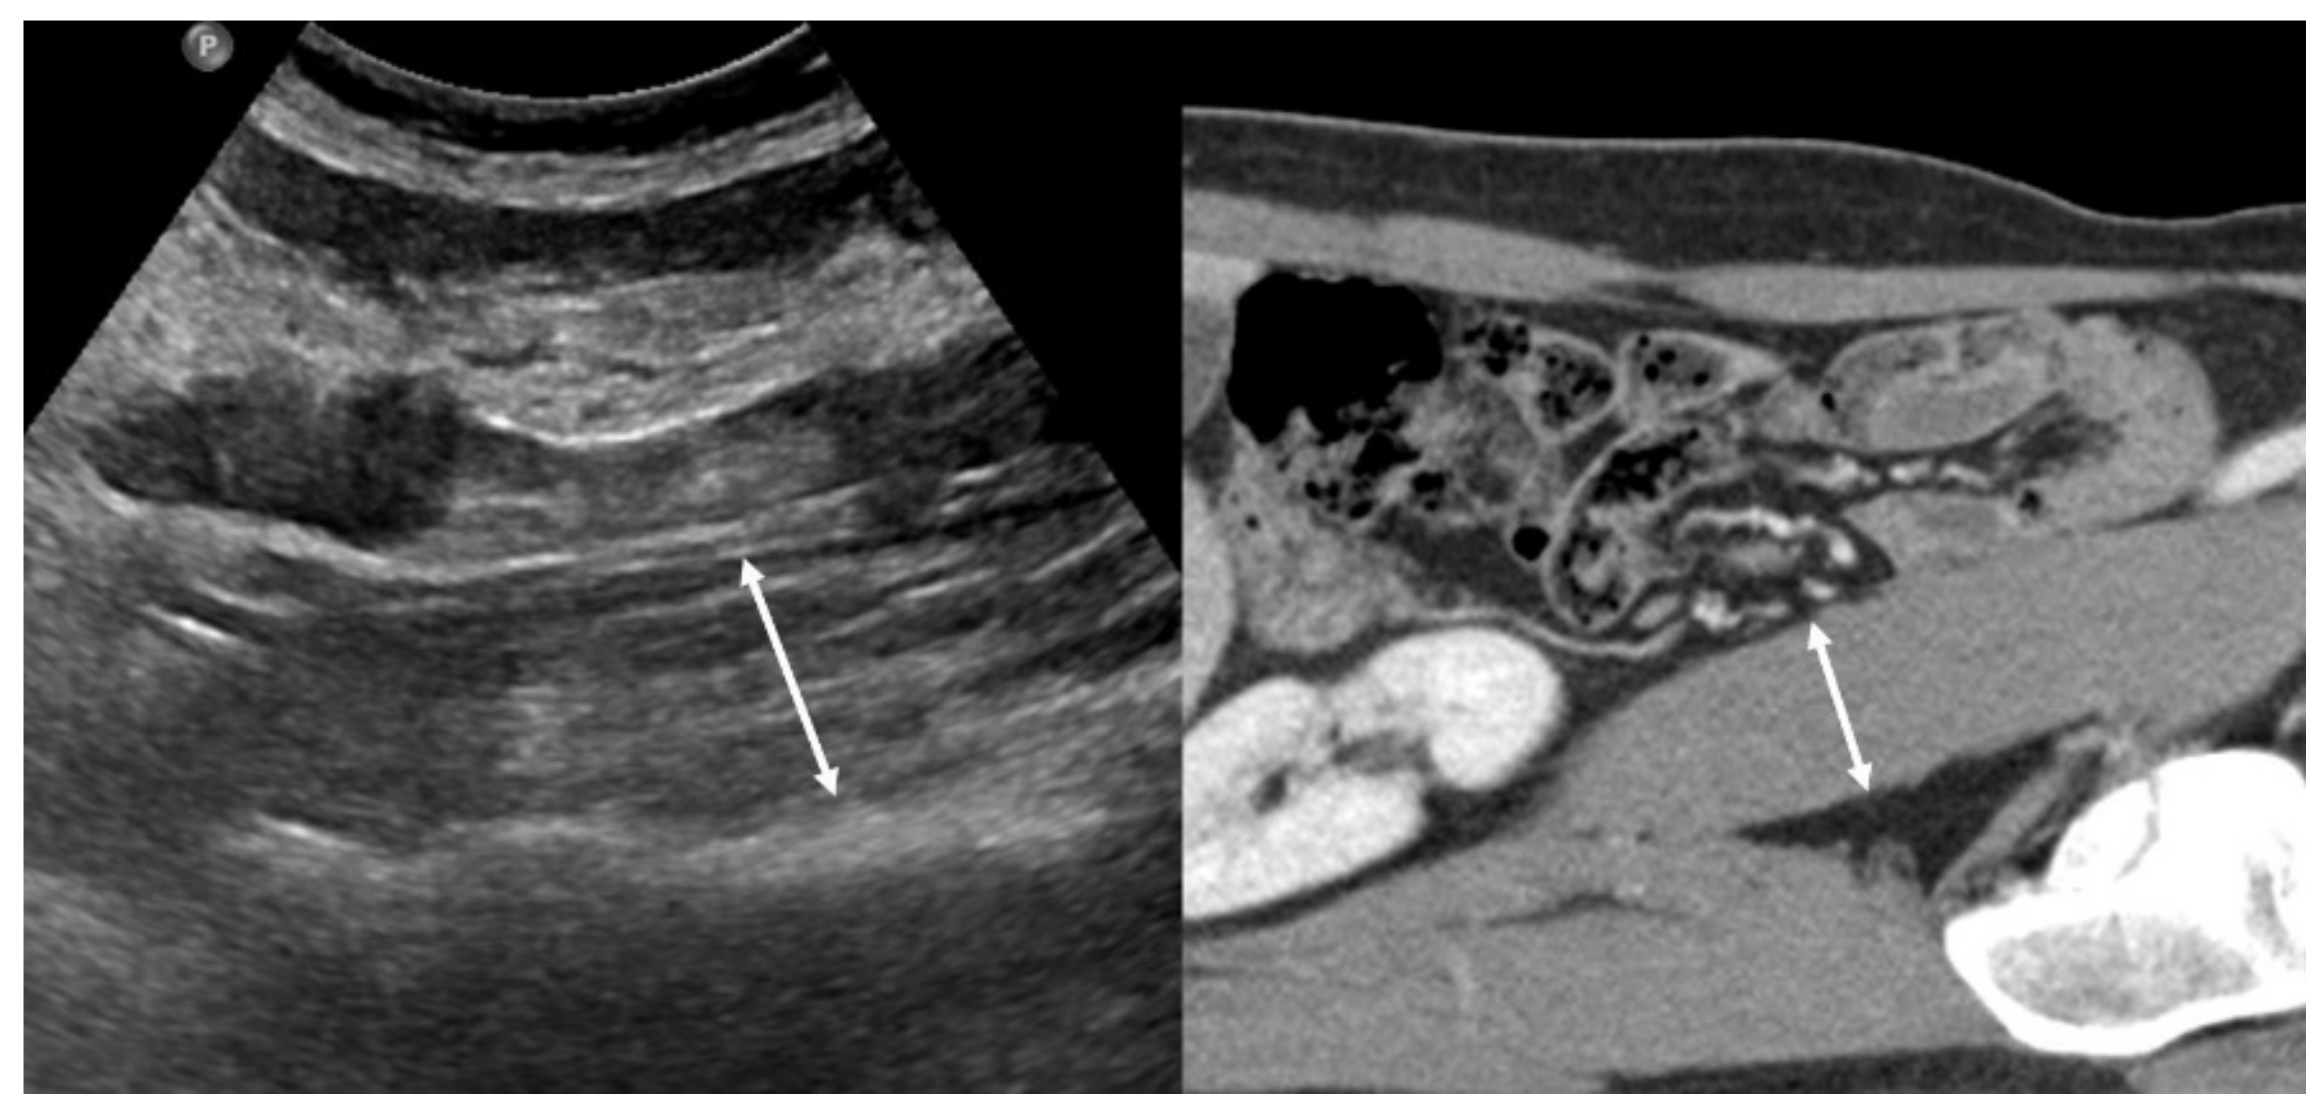

Tandon et al. demonstrated that a nomogram based on body mass index and right thigh muscle thickness can identify male and female patients with sarcopenia defined by cross-sectional CT [23]. Hari et al. showed the possibility of using US for the evaluation of sarcopenia in patients with chronic liver disease by measuring the diameter of the right psoas muscle [24] (Figure 2). The authors reported that the success rate of measuring the psoas muscle was 72%. Technical failure was due to a poor sonic window with a high abdominal circumference or the presence of ascites. US can be used as a screening tool for sarcopenia in situations where other imaging methods are not available because of their radiation, high cost, and lack of portability.

Figure 2.

Left side: Example of an ultrasound measurement of the psoas muscle diameter. Right side: the corresponding CT image.